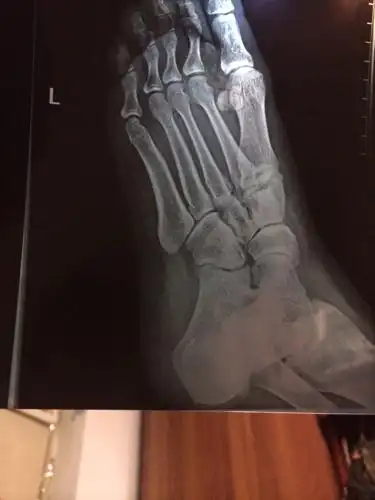

拍片子判断左足第一四跖骨基底部骨皮质连续性差,ct报告第四跖骨基